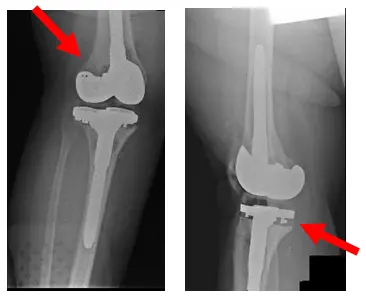

Patient was advised to have a left TKA Revision of the prosthesis, and since tests results came back negative for infection it only had to be a single staged reconstruction. All options and any other alternatives, along with all of the risks, were discussed with the patient.

X-Rays show postoperative changes of placement of left revision TKA

Post-operatively patient has presented to be doing very well and experiencing no pain. Patient has good range of motion and is weight bearing as tolerated.